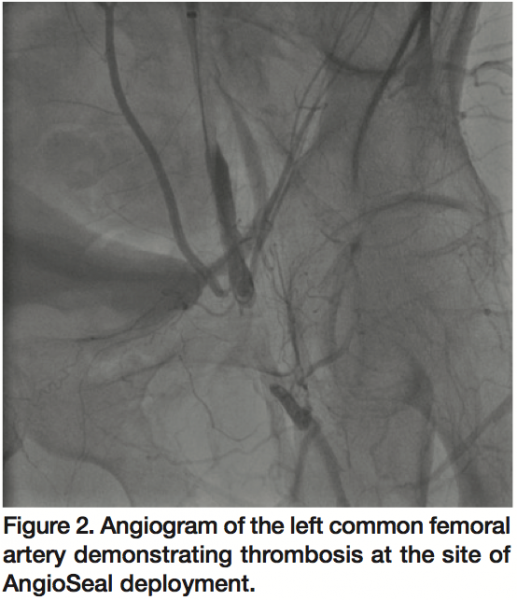

A 57-year-old male with history of hypertension, dyslipidemia, and prior coronary artery bypass grafting underwent successful percutaneous coronary intervention (PCI) via access from the left femoral artery. Upon completion of the procedure, a limited angiogram of the left common femoral artery revealed minimal disease (Figure 1) and a 6 Fr Angioseal vascular closure device (St. Jude Medical) was deployed successfully with adequate hemostasis. Vascular examination post-intervention was unchanged from baseline with resting left ankle-brachial index of 1.23. The patient was discharged on dual antiplatelet therapy including 325 mg aspirin and 75 mg clopidogrel without complications. Two months later, the patient presented with vague symptoms of burning and tingling involving his left thigh as well as typical symptoms of claudication.

Access was obtained in the right common femoral artery and selective left external iliac artery angiogram was performed, which confirmed hazy thrombotic occlusion of the left common femoral artery at the site of AngioSeal (St. Jude) deployment with reconstitution at the bifurcation of the left superficial femoral and profunda femoris arteries (Figure 2). With the support of a 4 Fr glide catheter, an angled Glidewire (Terumo Medical) was used to cross the occlusion into the distal superficial femoral artery (SFA) with a gradient of 50 mmHg across the occlusion. Rheolytic thrombectomy was then performed using an AngioJet catheter (Medrad Interventional) with multiple runs into the SFA (Figure 3) and profunda femoris artery with improvement in flow across the lesion but persistence of residual thrombus. The glidewire was then exchanged for a Confianza Pro 0.014 mm wire (Asahi Intecc) and laser atherectomy was performed using a 1.7 mm Turbo Elite laser catheter (Spectranetics) utilizing fluence/rate settings of 40/40, 60/60, and 60/80 serially (Figure 4) with further improvement of flow across the left common femoral artery.